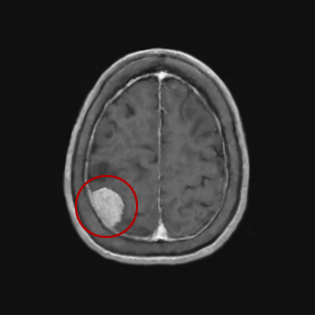

뇌하수체종양, 두개인두종, 뇌수막종, 척삭종, 청신경초종, 뇌종양

뇌종양, 뇌하수체종양, 두개인두종, 뇌수막종, 척삭종, 청신경초종

뇌하수체 종양

뇌하수체 선종, 두개인두종 등

두개저질환

척삭종 등